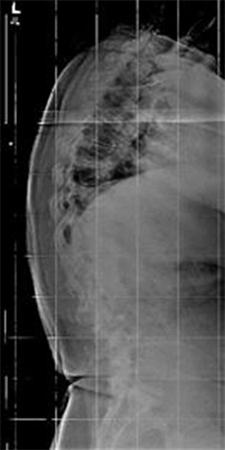

9. A 67-year-old man falls forward from standing height sustaining a hyperextension injury to his neck. He has neurological deficits present on physical examination. A radiograph, CT scan and MRI are seen in Figures A, B and C. Which of the following MOST likely characterizes his neurologic examination?"

FIGURES: A

B

C

DISCUSSION: The patient in the scenario has a central cord syndrome. The images show a relatively kyphotic spine with moderate osteophyte formation from C4 through C6. The MRI shows stenosis without cord signal change. Central cord syndrome is characterized by motor deficits more pronounced in the upper extremities than lower extremities. In addition, finger and wrist motor function is more affected than shoulder and biceps function. Sensory deficits are usually minimal.